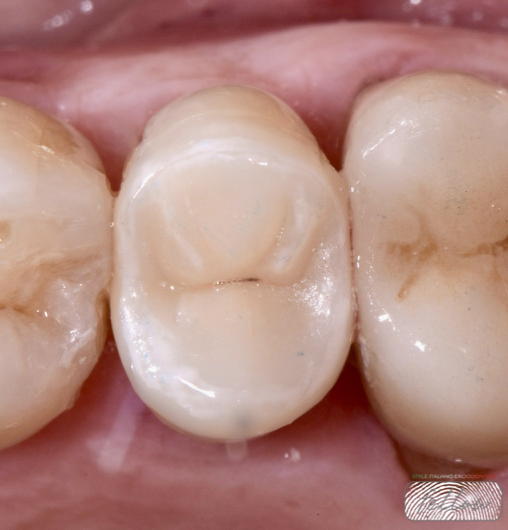

Fig. 1

Clinical image of tooth 25 showing a previous and extensive direct composite restoration.